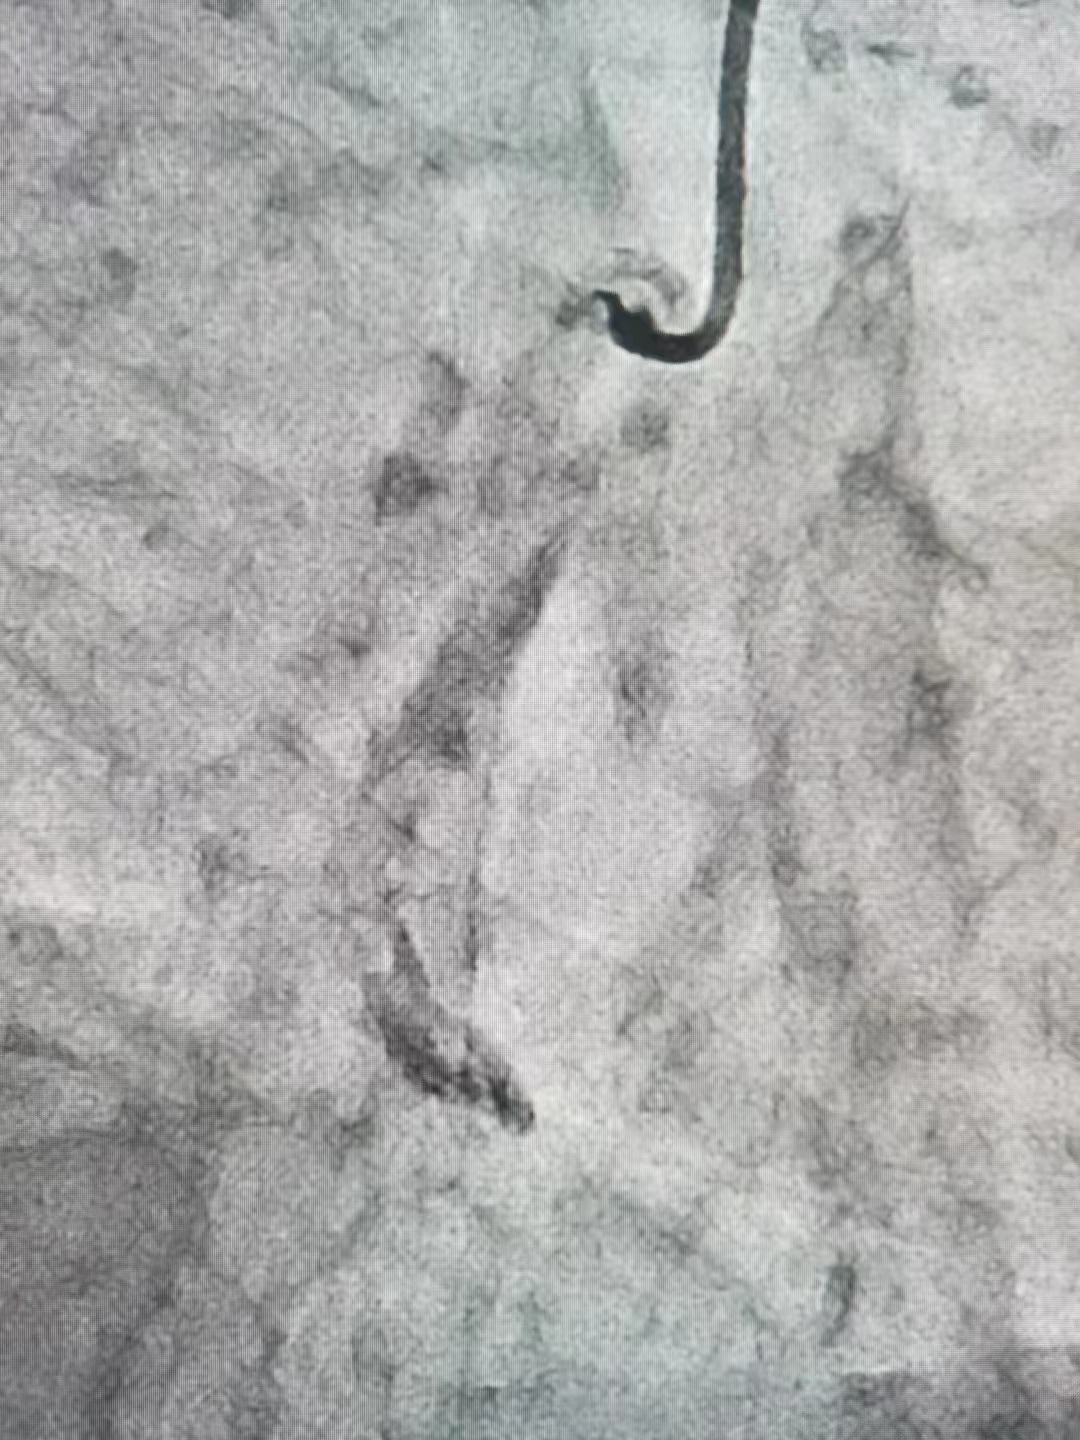

冠脉造影结果:LM外膜钙化,内膜不光滑,中段狭窄90%,TIMI3级。LCX外膜钙化,内膜不光滑,TIMI3级。RCA外膜钙化,内膜不光滑,近段狭窄80%,中段狭窄90%,可见破损斑块,TIMI3级。